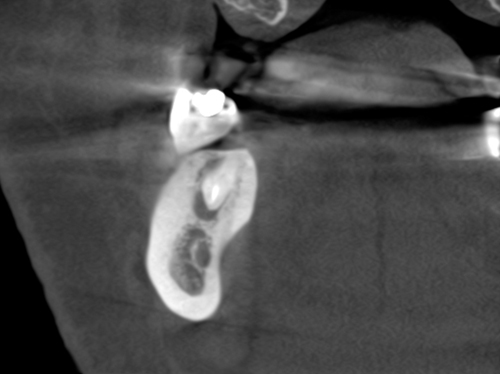

Nuestro paciente Eduardo Vicente Pedrós ha tenido en varias ocasiones infecciones en dientes que estaban desvitalizado. Él nos explica perfectamente en el vídeo que la cirugía periapical (o apicectomía) es un tratamiento que permite salvar la mayoría de los dientes afectados de esta patología.

Es una intervención técnicamente exigente, que requiere formación e instrumentos especializados (microscopio, endoscopio, etc.), pero que correctamente realizada no causa molestias prácticamente y tiene unos resultados exitosos en más del 90% de los casos.